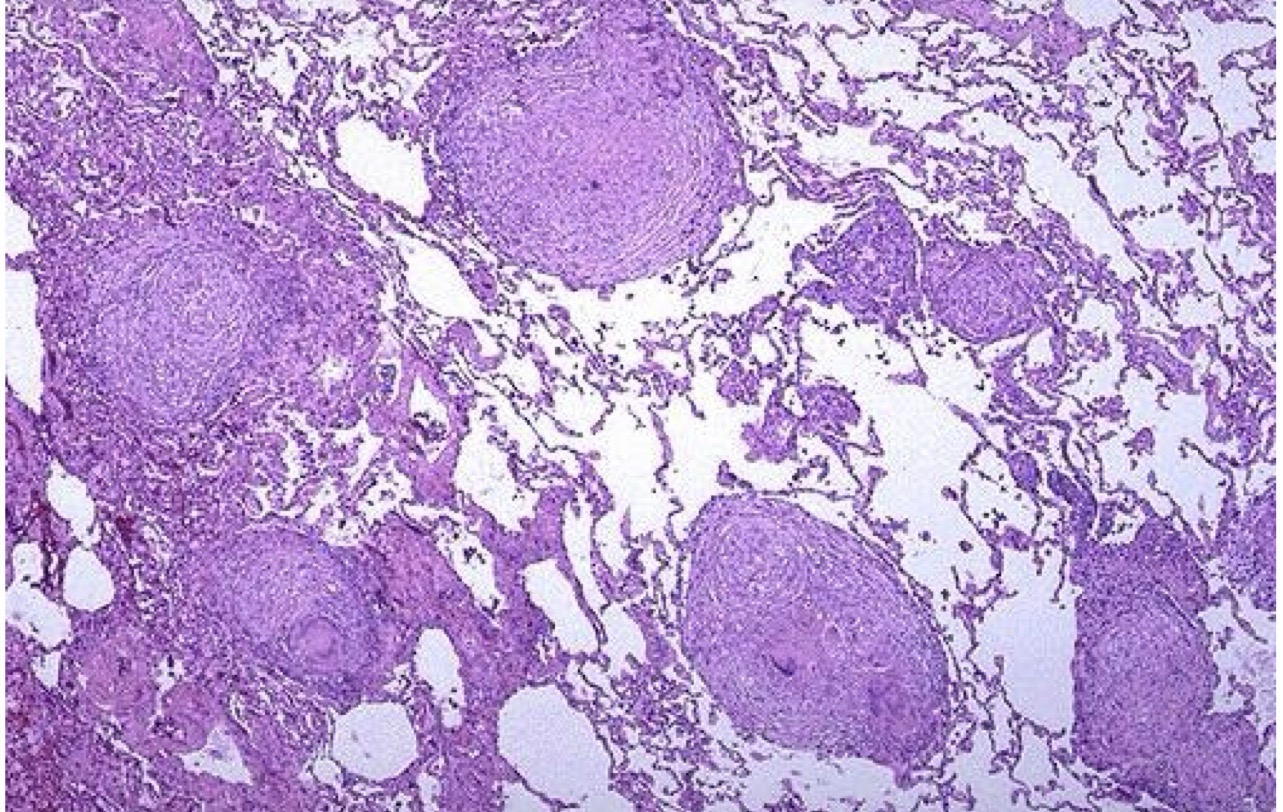

A- identify

B- describe

A- Granulomatous inflammation

B- Presence of scattered granulomas in the parenchyma.

B-Tow pulmonary granulomas , Consists of epithelioid cells, giant cells, lymphocytes, plasma cells, and fibroblasts.